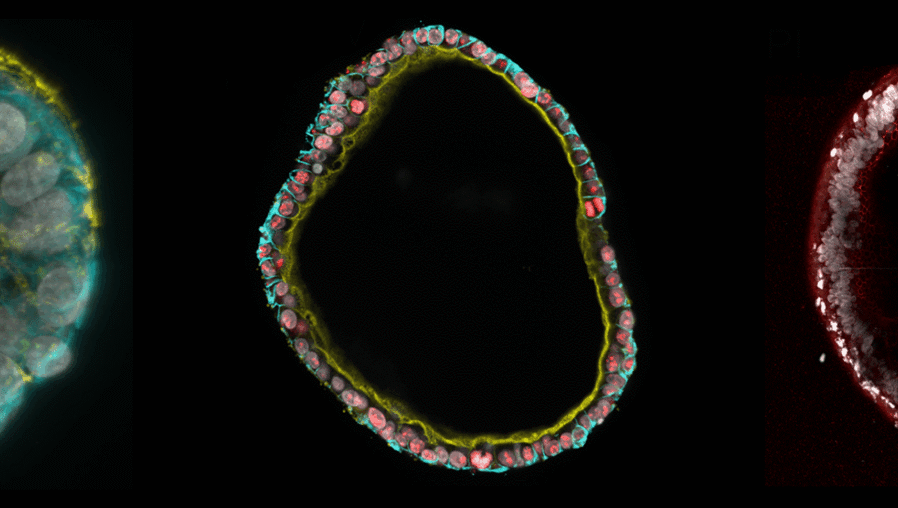

Researchers from the Hubrecht Institute and Radboud University have developed a completely animal-free gel to grow organoids, miniature three dimensional versions of organs. By combining the bacterial protein invasin with a synthetic gel known as polyisocyanopeptide (PIC), they created an environment in which organoids can grow and expand long-term, just as they do in animal-derived gels such as Matrigel. The study, published in PNAS, marks the first synthetic and animal-free system that enables long-term growth of 3D organoids.

Crucially, the team demonstrated that organoids grown in the PIC–invasin gel can be expanded continuously over long periods of time, while maintaining the same structure and cell types as organoids grown in animal-derived gels.

Organoids from a variety of human and mouse tissues grew successfully in the PIC–invasin gel, showing its robustness and potential for widespread use in both research and clinical settings.